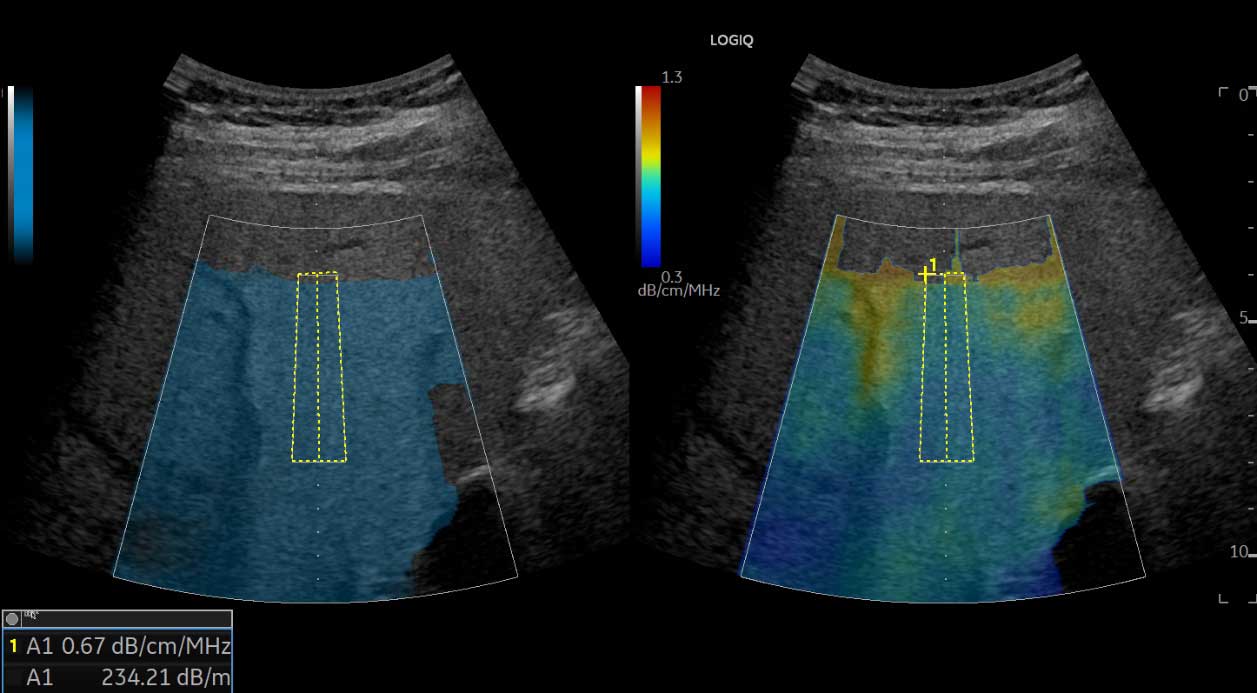

UGAP